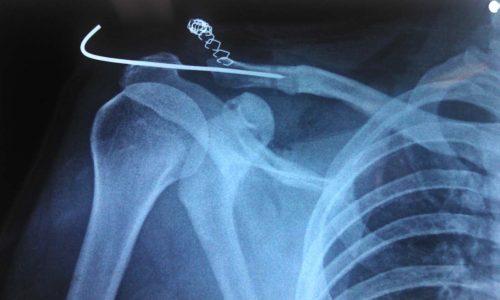

Cirugía mínimamente invasiva: artroscopia de hombro y codo.

Técnicas quirúrgicas avanzadas permiten tratar lesiones como las del manguito rotador, luxaciones recurrentes de hombro y epicondilitis mediante incisiones menores a 5 mm, reduciendo complicaciones y mejorando la estética de la cicatriz.

¿QUÉ PASA CUANDO OCURRE UNA LUXACIÓN ACROMIO – CLAVICULAR?

La luxación acromio – clavicular es una lesión frecuente en algunos deportes debido a trauma en el hombro. Hay una separación…